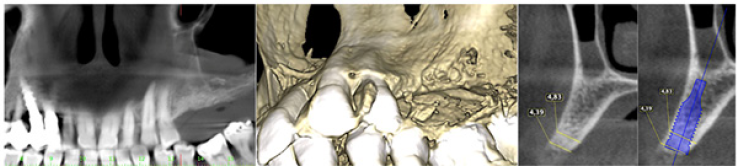

The patient was a woman 64-year-old with history of periodontal disease. Non-smoker, in good general health, she did not report allergies or intolerances to anesthetics and drugs. She presented with stage IV periodontitis and partial edentulism in the second quadrant with a horizontal bony deficiency. The first step represented full-mouth disinfection and systemic therapy with Metronidazole and Amoxicillin for 7 days to reduce the infection. After 3 months of good periodontal maintenance, the CBCT showed a defect where the thickness of the residual bone was less than 5mm. The thickness of the buccal plate prior to surgery was less than 1mm while minimum thickness recommended from evidence should be 2mm [19]. After local anesthesia with 4% Articaine with adrenaline 1:200,000, a crestal incision and a full-thickness vestibular flap with vertical incisions mesial to tooth 24 and distal at tuber level was elevated. A full-thickness palatal flap was also raised 10mm apically without vertical incisions. After obtaining adequate passivation of the buccal flap, decortications of the buccal bone wall were performed using the IM1S PiezoSurgery insert (Mectron, Carasco, Italy). IK 3.8x13mm and IK 3.8x11mm implants (Resista Group, Verbania, Italy) were placed in the sites 25 and 26. There were’t exposed threads, but the buccal bone wall was thin.

Figure 1: Initial status. Buccal plate concavity on the upper left quadrant.

Figure 2: The thickness of the bone was less than 5mm. The buccal bone wall at planned implant position was less than1mm thick.